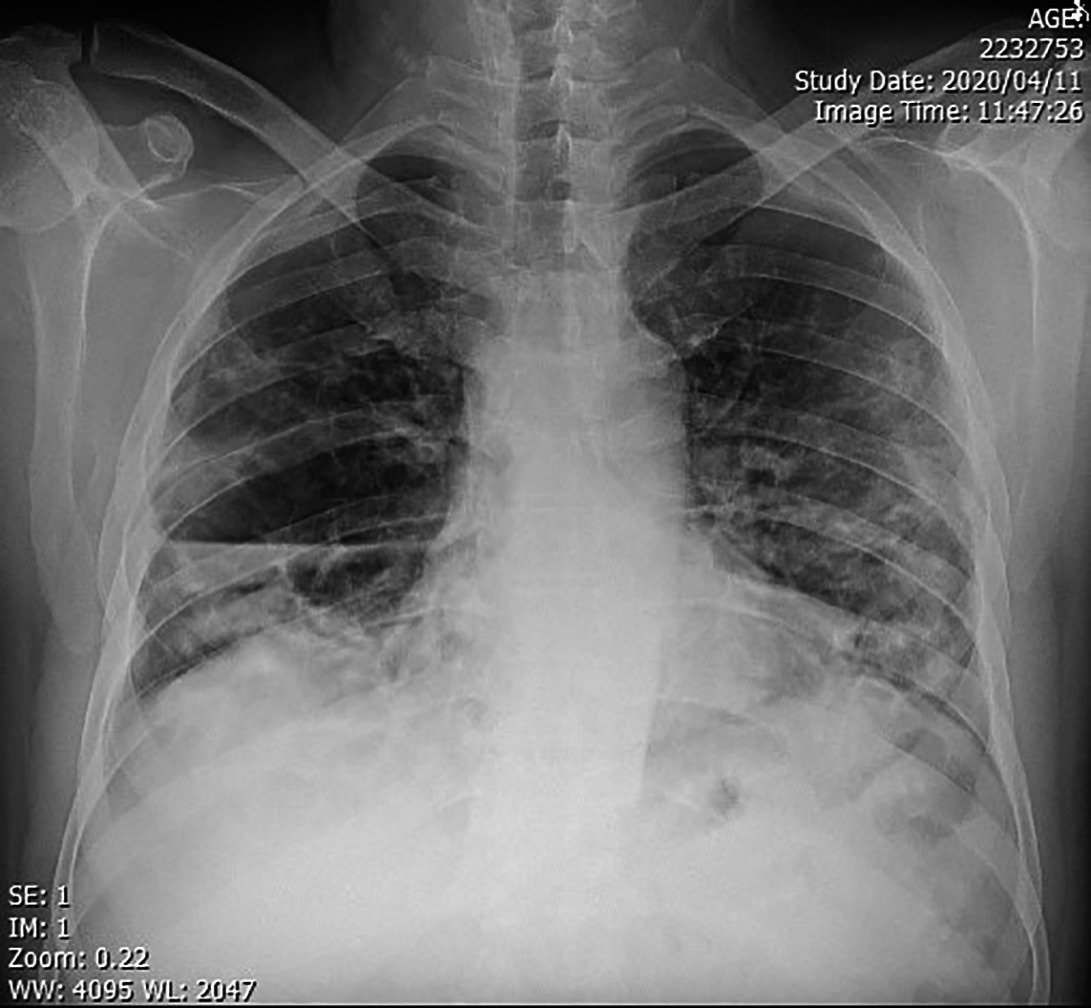

- X-ray chest (P/A view): Showing a well circumscribed area of dense opacity with cavitation & air fluid level.